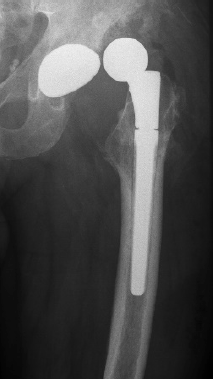

In August 2013 THA was performed due to a girdlestone situation after septic osteoarthritis of the hip (Figure 1) in a 46 year old male patient using a MRP Titan revision stem (Diameter: 18mm, length: 140 mm) (Peter Brehm GmbH, Weisendorf, Germany) and a cementless cup (Allofit - IT; Diameter 54 mm, Zimmer, Warsaw, USA) and a ceramic on ceramic bearing (head diameter: 36 mm) (Figure 2). The patient was 175 cm tall and weighed 105 kg (body mass index: 34.3 Kg/ m2). 2 weeks later revision surgery due to recurrent dislocation (Figure 3) was performed. Revision of the acetabular component was done using an Allofit - Classic- cup, Diameter 56 mm (Zimmer, Warsaw, USA)). The neck component was exchanged from small to medium size (Figure 4). A ceramic on PE bearing was implanted (head diameter: 32 mm). Postoperative healing was uneventful. The patient was out of any complaints. In February 2016 the patient started suffering from slight thigh pain but detected crepitation in the region of the left hip. X-ray of the left hip in 2 planes in May 2016 revealed an asymmetrically gap of the stem / neck junction (Figure 5). During revision surgery of the left hip breakage of the cone of the morse taper junction was visible (Figure 6). Removal of the well-fixed stem was performed via a distal fenestration. After fixation with cerclage wires a bended MRP Titan revision stem (Diameter: 19 mm, Length: 200mm with long neck and extension sleeve) was implanted using a 32 mm ceramic head (Figure 7). Postoperative healing was uneventful.

Figure 1. X-ray of the left hip in 2 planes: ap view a. and lateral; b. view shows a girdlestone situation following septic arthritis of the left hip with staph. aureus.